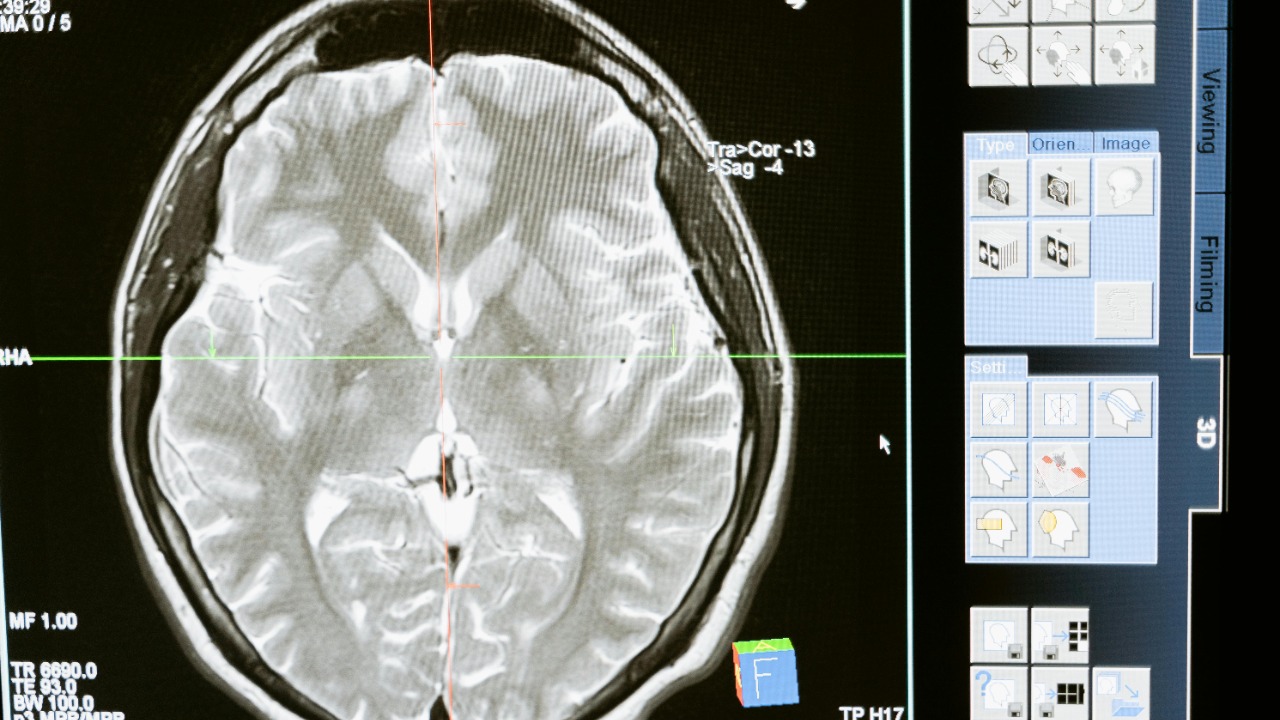

In public reporting, these experts describe a spectrum of potential brain-directed tools, from chemicals that subtly alter cognition to devices that bombard neural tissue with focused energy. They stress that the same knowledge that allows doctors to treat depression or epilepsy can be repurposed to disrupt attention, induce confusion, or heighten fear in targeted populations. That concern is reflected in detailed accounts of mind-altering brain weapons that are no longer dismissed as fantasy, and in parallel calls from other scientists who frame these developments as a wake-up call for governments and security institutions.

Researchers who work with neurochemistry and neuromodulation have started to spell out how this dual-use risk might play out in practice. They point to pharmacological agents that can dampen memory formation or heighten suggestibility, and to noninvasive stimulation methods that can alter mood or attention without breaking the skin. Reporting on scientists issuing a wake-up call over these mind-altering tools underscores that the concern is not abstract: it is rooted in specific mechanisms that are already being tested in clinical and research settings, and that could be repurposed with relatively modest changes in hardware or delivery systems.